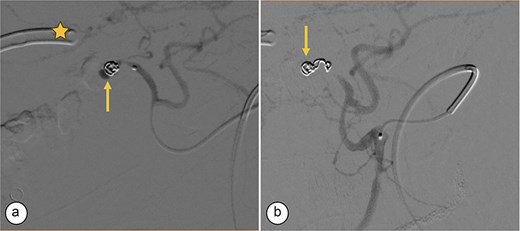

Transcatheter arterial embolization of the right hepatic artery. (a) Selective transcatheter arterial embolization (TAE) of the branch of the right hepatic artery (Segment V) (arrow). (b) Post-embolization image of the pseudoaneurysm in the branch (Segment V) of the right hepatic artery with microcoils (arrow), showing no contrast medium leakage. Right percutaneous catheter (star).